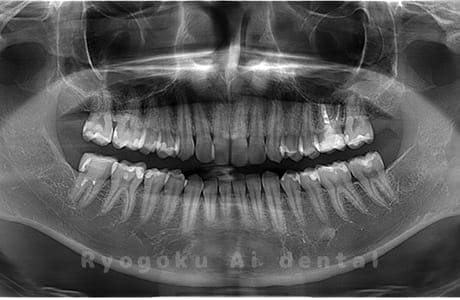

Case02

- 原因

- 下顎の水平埋伏智歯

- 治療内容

- 下顎の水平埋伏智歯を抜歯

<リスク・副作用>

手術後は痛み、腫れ、痺れなどの副作用が生じる場合があります。